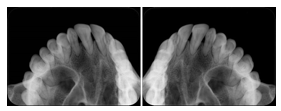

2 Occlusal Vertical Maxilla A Dental Image Layout

DL-C001A

Reference: DL-C001-U1L0

Reference: DL-C001-U2L0